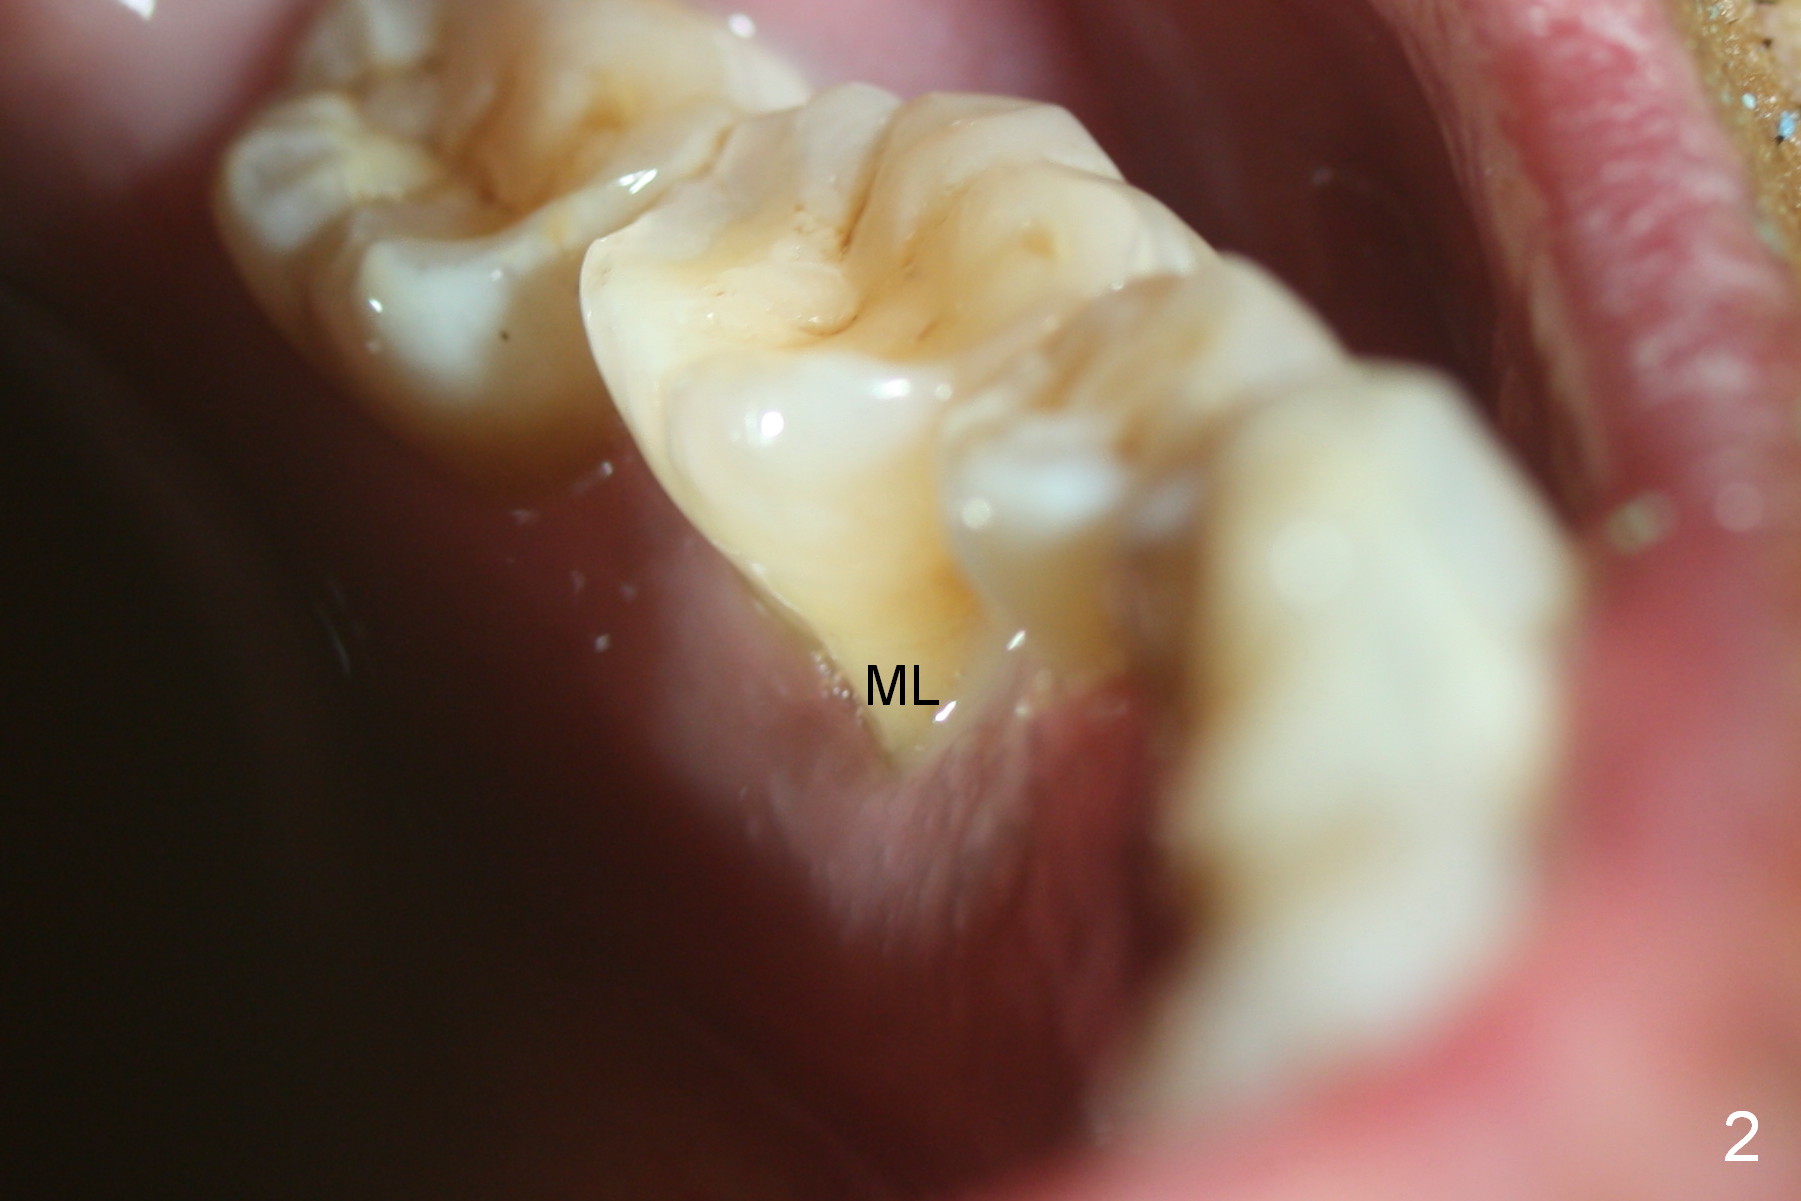

Considering the severe bone loss in the meisal socket, socket preservation is indicated if immediate implant is not feasible. Preop exam shows that the mesiobuccal gingival recession (Fig.1 MB) is not as severe as the mesiolingual one (Fig.2 ML). Because of oozing from the mesial socket, buccal envelop incision is made with flap raising to increase visibility. Probably due to periodontal infection, pain control is difficult. Osteotomy buccal to the Inferior Alveolar Canal proves to be risky. In addition, osteotomy in the mesial socket is more difficult than the distal one (Fig.3). Once the osteotomy depth is determined relative to the superior border of the Inferior Alveolar Canal (4 mm), the osteotomy depth increases by 2 mm. A 5.5x10 mm implant is placed with insertion torque ~ 35 Ncm (Fig.4); a 15 ° angled abutment (5.5 mm in diameter, 4 mm in cuff) is placed mesially. Then the abutment is turned lingually favorable for restoration (Fig.5), the remaining socket is filled with allograft/Osteogen (*) and Collagen Plug.

There is calculus over the mesial root of the extracted tooth (Fig.7,8).